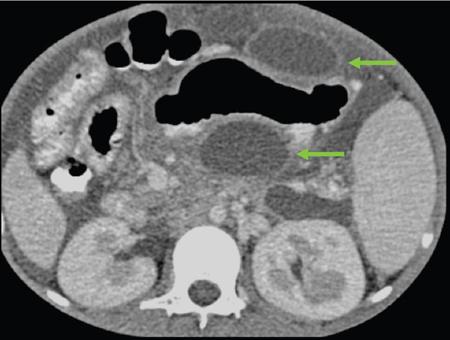

Anirudh Kohli Acute pancreatitis is one of the most dreaded diseases to afflict mankind, in view of its high morbidity and mortality. The single most important factor in reducing the morbidity and mortality of this condition over the last many years has been the role of computed tomography (CT). The incidence of acute pancreatitis is rising especially due to an increasing incidence of gallstones, obesity, as well as an ageing population. Pancreatitis occurs due to a chain of events triggered by a temporary/permanent pancreatic duct obstruction. This leads to activation and release of pancreatic enzymes into pancreatic interstitium and peripancreatic tissues leading to severe auto digestion and necrosis of pancreas and adjacent tissues. Systemically there is release of inflammatory mediators known as cytokines. Tumour necrosis factor is a cytokine which is toxic to acinar cells. These cytokines activate and intensify the inflammatory cascade that may ultimately culminate in multiorgan failure. Clinically severe acute pancreatitis is characterized by two phases, an early phase and a late phase. The early phase is dominated by the systemic effects of release of inflammatory mediators such as cytokines – termed as systemic inflammatory response syndrome (SIRS). Usually there is associated variable multiorgan dysfunction/failure. This phase lasts for a week. When the multiorgan failure lasts 2 days it is termed as mild, multiorgan failure lasting more than 48 hours is considered severe. There is no correlation between the clinical severity of pancreatitis and morphological changes in this early stage. In view of this CT scan is not of much utility during this phase, unless complications are suspected. The later phase is dominated by effects of local complications due to pancreatic/peripancreatic necrosis. Mortality follows this biphasic pattern in early weeks from the systemic effects of multiorgan failure and in later weeks due to local effects, for example infection of necrotic pancreatic/peripancreatic tissues superimposed by organ failure. The Clinical diagnosis of acute pancreatitis requires two of the following three features: If the first two findings are present without any significant SIRS then CT is not required. Acute pancreatitis is a complex disease with a wide variation in the presentation and outcome, ranging from asymptomatic with only biochemical alterations to a fatal outcome. In fact acute pancreatitis is a dynamic disease with continuously evolving appearances on imaging. There are two distinct forms of acute pancreatitis – interstitial oedematous pancreatitis and acute necrotising pancreatitis. Interstitial oedematous pancreatitis is a condition where there is only mild swelling of the pancreas with loss of normal lobulations and a diffuse decrease in attenuation of the pancreas. There may be heterogeneity of the pancreatic parenchyma due to varying degrees of interstitial oedema. This form of pancreatitis runs a mild course and rarely progresses to acute necrotising pancreatitis with its associated complications. In a third of these cases the pancreas may reveal no abnormality on a CT scan. The inflammatory changes may be restricted to the pancreas or extend into the peripancreatic regions. The inflammation in the peripancreatic regions manifests as acute pancreatic effusions. If there is peripancreatic fat necrosis with an oedematous pancreatic gland it is termed as acute necrotising pancreatitis (Figs. 9.17.1–9.17.2). Acute pancreatic fluid collections are enzyme-rich pancreatic juice collections seen in about 40% of patients with acute pancreatitis. The fluid collections occur due to exudation of pancreatic juices into the interstitium of the pancreas and subsequently leakage into the surrounding tissue spaces. These fluid collections are localized only by the anatomic space in which they collect. As the exudative process continues, the parietal peritoneum overlying the pancreas may be disrupted with the inflammatory fluid entering the lesser sac. From the lesser sac the fluid can enter the peritoneal cavity via the foramen of Winslow or by dissecting the peritoneum along the anterior surface of the lesser sac. Posterior extension of the fluid collection in the anterior pararenal space may occur into a potential space between the laminae of the posterior pararenal fascia. Rarely there may be involvement of the perirenal and posterior pararenal spaces. Other pathways of dissection are along the gastrohepatic, gastrosplenic and gastrocolic ligaments. Fluid may dissect along the root of the mesentery into the transverse mesocolon. Collections may extend around the caecum, ascending colon, descending colon and into the lumbar, pelvic and inguinal regions. Large fluid collections may dissect superiorly into the mediastinum or pericardial space. The quantity of fluid in these effusions is variable and can range from a small amount to large quantities (Fig. 9.17.3). Of these collections, 50% resolve spontaneously; the remainder may evolve after 4–6 weeks into pseudocysts. As the collections age, they tend to get localized and walled off, often developing an enhancing wall. A collection should be termed a pseudocyst only when a definite capsule develops and the collection has been static for at least 4–6 weeks. The risk of complications such as rupture, infection and haemorrhage increases with the age of the collection. Large collections of fluid are usually associated with a lesser degree of pancreatic necrosis as compared to extensive pancreatic necrosis associated with a lesser amount of fluid collection. Acute necrotising pancreatitis is a fulminant form of pancreatitis in which there is necrosis of the pancreas, that is nonviable pancreatic tissue. A contrast-enhanced CT is essential as it is the ideal means to demonstrate necrosis as well as to determine the extent of necrosis. These areas of nonviable pancreatic tissue do not enhance as compared to viable pancreatic tissue, which demonstrate significant enhancement. The extent of pancreatic necrosis has been found to correlate extremely well with the extent of necrosis found at surgery. The size, location and extent of pancreatic necrosis are very variable. These areas may be diffuse or focal, small in size to complete glandular involvement. These necrotic areas have a very important bearing on the course of pancreatitis, as they are liable to undergo secondary infection and form pancreatic sepsis. In addition, the more extensive the pancreatic necrosis the greater is the morbidity and mortality. Patients with no pancreatic necrosis have been found to have a 0% mortality and a 6% complication rate, whereas patients with pancreatic necrosis have a 23% mortality rate and an 82% complication rate. A variety of laboratory tests are available to detect pancreatic necrosis, such as a rise in the serum methemalbumin, quantitative estimation of C-reactive protein and urinary trypsinogen-activated peptide. CECT is still the most accurate modality to detect pancreatic necrosis. Pancreatic necrosis may be seen in the pancreas only, peripancreatic tissues also or only in the peripancreatic region. Isolated peripancreatic necrosis occurs due to disruption of the peripheral ductules with extravasation of activated pancreatic enzymes, may be seen in up to 20% of patients who require operative/interventional management of their necrotising pancreatitis. These patients with only peripancreatic necrosis have a better prognosis. This essentially represents retroperitoneal fatty tissue necrosis appearing as heterogeneous areas of liquid and nonliquid components. Over time necrosis evolves and liquefies as well as the liquid component resorbs. Generally if the liquid component is 2 cm or less it will resorb, while fluid collections 5 cm or more rarely resorb. If pancreatic necrosis is not resorbed it may get walled off or with time or may become infected. Encapsulation occurs between the third and fourth weeks. It is important to differentiate sterile from infected necrosis as sterile necrosis rarely needs surgery, whereas infected necrosis requires long-term antibiotic therapy and/or some kind of imaging/surgical intervention. According to the Atlanta 2012 classification, all areas of pancreatic necrosis are termed as acute necrotic collections. This represents a combination of pancreatic/peripancreatic fat necrosis with peripancreatic effusions. On CT, there is a spectrum of findings – solid, liquid containing debris (these may be nonwalled off/partially walled off). Sonography and MRI have advantages over CT scan in demonstration if the contents are pure liquid such as acute pancreatic effusions or have some nonliquefied components such as acute necrotic collections. Pseudocysts are round or oval encapsulated fluid collections containing only liquefied components. It takes 4 weeks for the granulation tissue to develop. On CT, a pseudocyst appears as a well-defined fluid collection with a thin capsule. The most common location for pseudocysts is the lesser sac, though they may be found anywhere in the mediastinum, abdomen or pelvis as they may dissect along fascial planes, along vessels and through capsules of solid organs. Pseudocysts in the bowel, though reported, are relatively rare, as the bowel wall is a strong barrier to the effect of proteolytic pancreatic enzymes. When the contents of the pseudocyst are heterogeneous or uniformly increased in attenuation, the possibilities of infection or haemorrhage should be considered. Focal areas of increased density within the fluid collection usually indicate haemorrhage. Complicated, enlarging or symptomatic pseudocysts require percutaneous catheter or surgical drainage. Infected pseudocysts are treated by percutaneous drainage. The management of a noninfected pseudocyst is controversial. Surgical treatment is only undertaken when the wall is mature after several weeks. Large pseudocysts greater than 5 cm in size can easily be drained percutaneously using intercostal drainage tube or pigtail catheter or endoscopically via the stomach. The cure rates are reported to be 85% with percutaneous drainage, the drainage period averaging about 20 days (Figs. 9.17.4–9.17.5). Walled off necrosis – as pancreatic/peripancreatic necrosis matures and evolves, an interface develops between necrosis and adjacent fatty tissue and an enhancing thickened wall is seen, resulting in a well-defined fluid collection with necrotic debris and fat necrosis. This is the end stage in the evolution of an acute necrotic collection. It is important to differentiate a pseudocyst from walled off necrosis, as a pseudocyst requires drainage and walled off necrosis requires surgical removal (Figs. 9.17.6–9.17.9). Sepsis is a major complication of pancreatitis and is accompanied by a high incidence of mortality and a prolonged hospital stay. Pancreatic sepsis may occur following secondary infection of pancreatic and/or peripancreatic necrosis, acute pancreatic fluid collections and pseudocysts. The only specific sign to demonstrate sepsis is the presence of gas in a collection. This occurs due to secondary infection by coliform/anaerobic organisms. This sign is unfortunately not common and seen in only one-third of cases. Gas is seen in the fluid collection as very dark well-defined air attenuation bubbles. Occasionally gas may be present due to a gastrointestinal fistula or previous surgery. Fat necrosis is seen in peripancreatic collections. This should not be confused with air bubbles, which are indicative of sepsis. The differentiation is easy to understand by CT, the values of fat ranging between – 20 HU and – 80 HU, and of air being >–300 HU. Also air bubbles have well-defined margins and are homogeneously jet black, whereas fat is nonhomogeneously grey with ill-defined margins. Since the presence of air is seen only in a small percentage of patients with pancreatic sepsis, the only other means to diagnose pancreatic sepsis is by CT-guided aspiration. All sites of fluid collection, parenchymal necrosis and peripancreatic necrosis are subjected to CT-guided aspiration. This is a tedious process and requires a dedicated interventional radiologist as there are often more than 5–6 sites from which it may be necessary to obtain samples. A fresh needle and syringe are used for each site, as it is important to know which site has sepsis and which is sterile. Care is taken not to transgress the large bowel as the colon has a large number of bacteria, and transgressing it could result in colonic bacteria contaminating the CT-guided aspiration sample, with falsepositive results. Further, colonic bacteria may be inoculated into a sterile acute pancreatic fluid collection or necrosis thereby converting a sterile collection into an infected one (Fig. 9.17.10). Complications of the procedure can be pneumothorax if the pleura is transgressed, haemorrhage due to trauma to a vessel, and secondary infection. Pancreatic sepsis is treated by surgical debridement, necrosectomy and drainage through thick tubes. It is crucial from the management point of view to differentiate an abscess from infected necrosis. An abscess may be treated by percutaneous drainage, whereas infected necrosis developing in relatively solid tissue can be treated by surgical debridement alone. Imaging-guided percutaneous drainage is the first step in treating pancreatic sepsis especially patients who are very ill and cannot undergo surgery. Initially pig tail catheters were used but these are notorious to get blocked as the largest bore of a pigtail catheter is 12 F. Pancreatic sepsis contains a large amount of necrotic debris, this blocks the catheters can be cleared by flushing the catheter, but this always raises the possibility of introducing secondary infection. To circumvent this issue large-bore ICD catheters have been introduced. These range from 16 F to 30 F. A safe window is necessary, not transgressing bowel or vasculature. It is quite easy to insert these tubes percutaneously under CT. A bit of initial manipulation and force is required to pierce the abdominal musculature. These large-bore drainage tubes have been very effective unless the infected necrosis is solid with minimal liquefied contents or a safe window for placing an ICD catheter is not available. CT is also invaluable in surgical planning and in the follow-up of postoperative patients to evaluate any fresh collection and also to determine whether the drains are well sited or not (Fig. 9.17.11).